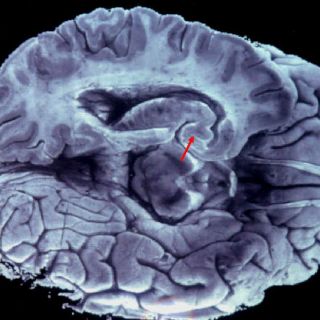

Se trata de una enfermedad crónica y desmielinizante que perjudica al sistema nervioso central y, por consiguiente, provoca discapacidad debido al daño ocasionado en la mielina que recubre las fibras nerviosas.